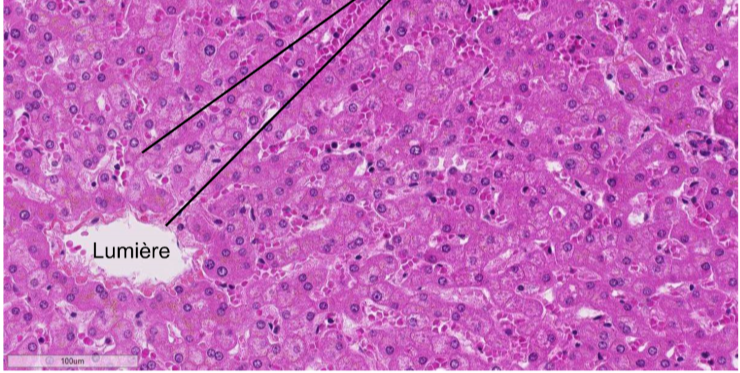

De quelle lame il s’agit et qu’est ce que les flèches montrent

Lame du foie au HES

on y retrouve des fibres réticulés (collagene type 3) peu visible dans cette coloration surtout autout du vaisseau et au niveau de la charpente